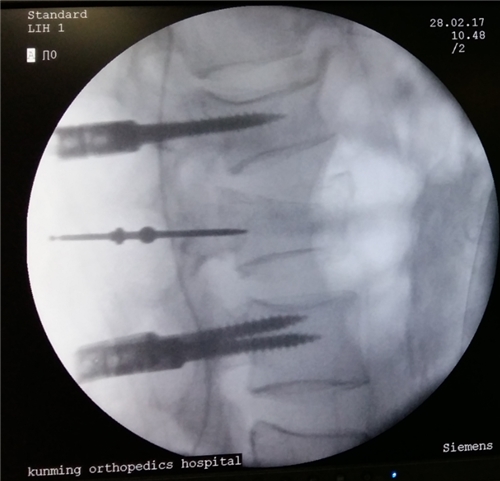

4、老年人治疗骨质疏松为时已晚:很多老年人认为骨质疏松无法逆转,到老年期治疗已经没有效果,为此放弃治疗,这是十分可惜的。老年人一旦确证为骨质疏松,应接受正规治疗,越早越好,这样可以减轻痛苦,提高生活质量。

5、治疗骨质疏松,只要补钙就行:骨质疏松的治疗不是单纯补钙,而是综合治疗,包括提高骨量、增强骨强度和预防骨折等。